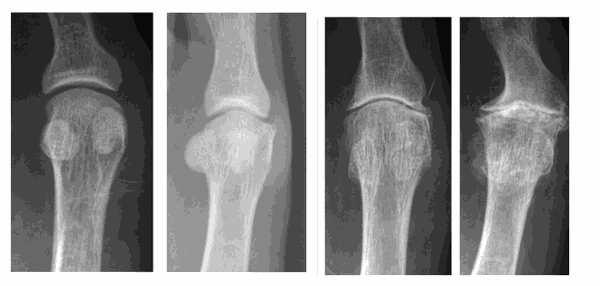

The pictures below show: 1st = normal – 2nd = mild – 3rd = moderate – 4th = severe hallux limitus.

This is made by clinical examination and X-rays. The severity of the joint disease on X-ray can vary from mild to severe, although this does not necessarily correlate directly with the symptoms experienced.